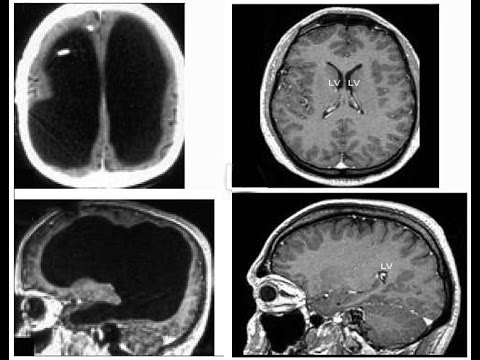

In 1980, Roger Lewin published an article in Science, "Is Your Brain Really Necessary?", about Lorber studies on cerebral cortex losses. He reports the case of a Sheffield University student who had a measured IQ of 126 and passed a Mathematics Degree but who had hardly any discernible brain matter at all since his cortex was extremely reduced by hydrocephalus. The article led to the broadcast of a Yorkshire Television documentary of the same title, though it was about a different patient who had normal brain mass distributed strangely in a very large skull.